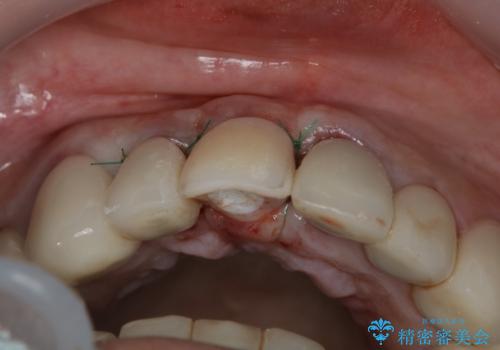

- 事故による外傷で前歯に歯根が真っ二つに折れてしまい、保存不可能となってしまった部分にインプラント治療を計画しました。

患者様のご要望もあり、審美性の確保ができる抜歯早期埋入→埋入後即時荷重という手術法を取りました。

従来、前歯部分のインプラントでは周囲に残っている自身の歯に仮歯を張り付けることで審美性を保ってきましたが、脱離を繰り返したり食事に耐える強度を保つのが難しいという側面がありました。

それと比較すると、今回の方法では骨にしっかりと固定されているインプラントに単独で仮歯を装着することができるためフロスも通せますし、ある程度負荷のかかる食事も気にせずできるようになります。